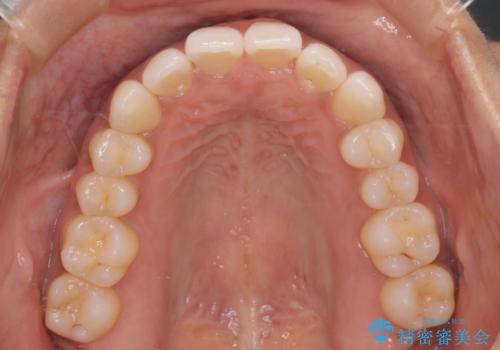

【インビザライン】前歯をきれいな歯並びにしたい

- 前歯の叢生を主訴に来院されました。このケースは抜歯をせずにIPRにてスペースを確保し、並べる計画をたてました。

きちんと使用時間を守って使用していただいたことで短い期間で治療が終了しました。